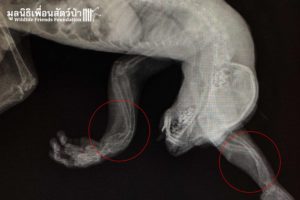

The Veterinary Team did an initial examination and x-ray, they found Tufa has a severe case of metabolic bone disease (MBD) which is commonly found in most vertebrates. MBD is caused by improper nutrition, calcium deficiency, and vitamin D deficiency. In this case, Tufa’s limbs are deformed and in a fragile state which makes it very difficult for him to crawl or climb in a tree the way a slow loris is supposed to.

ทีมสัตวเเพทย์ได้ตรวจร่างกายพร้อมกับ X-ray จึงพบว่า ทูฟาเป็นโรคกระดูกเมตาบอลิกหรือโรคกระดูกพรุนซึ่งสามารถพบได้บ่อยในสัตว์เลื้อยคลานหรือสัตว์ที่มีกระดูกสันหลังทุกชนิด ส่วนใหญ่เกิดจากสัตว์ที่ไม่ได้รับสารอาหาร วิตามิน หรือเเสงเเดดที่เหมาะสม อย่างในเคสนี้ทำให้กระดูกของทูฟาโค้งผิดรูป บางลง เเละอยู่ในสภาพอ่อนเเอ สามารถคลานหรือปีนต้นไม้ได้อย่างลำบาก